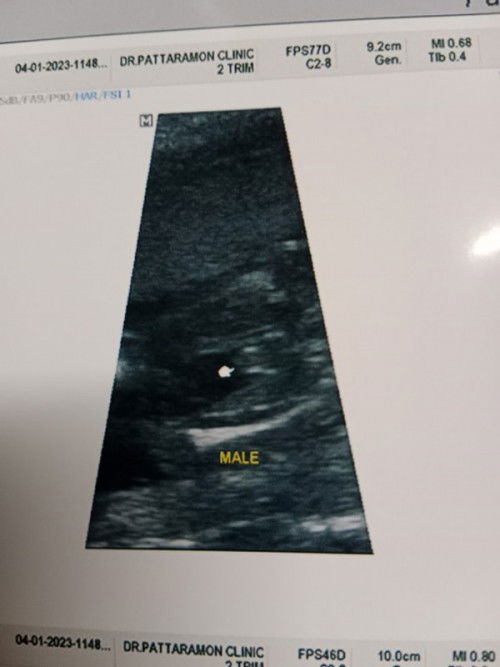

ผช.จริงๆใช่มั้ยย?😅

พอจะเป็นสายสะดือได้มั้ยคะ อีแม่อยากได้ญ.มากก♥️😂 ปล.คนแรกผช.แล้ว #คุณแม่ลูก2